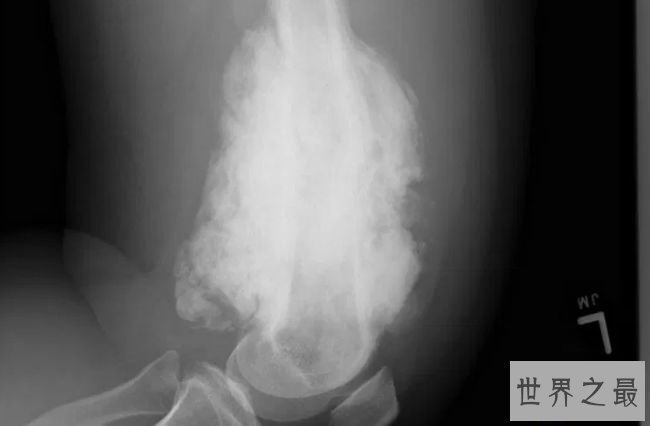

5.蜡泪样骨病

人类骨骼中最不常见的疾病之一是蜡泪样骨病,这种疾病在人类中十分稀有。在这种疾病中,一种十分巩固的骨头会在已经存在的骨头上以不规则的模式生长,在x射线钻研中,这种骨骼的生长看起来像蜡烛外表的蜡泪。